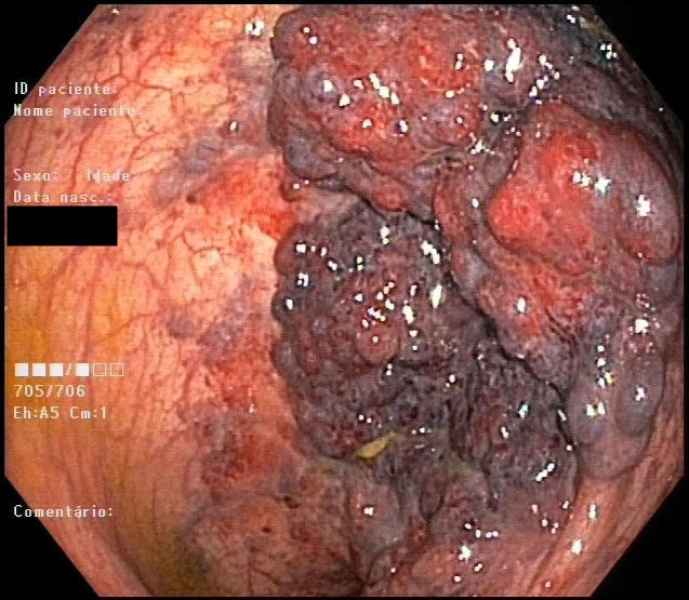

Colonic metastasis of cutaneous melanoma

Fotografia